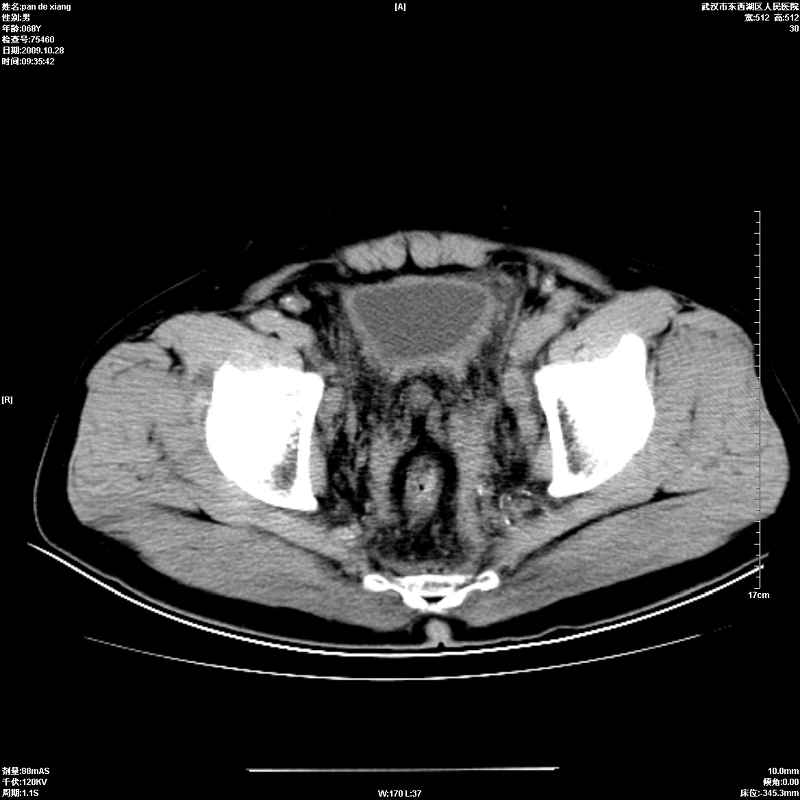

以下是引用杀毒软件在2009-10-28 20:41:00的发言:[br]结合临床考虑---白血病双肾改变或淋巴瘤。

以下是引用zxl51642在2009-10-29 9:59:00的发言:[br]结合临床“单克隆免疫球蛋白血症”,考虑双肾为继发损害并肾功能不全(尿中大量igg及少量iga、igm等大分子免疫球蛋白滤出所致继发损害),椎前软组织肿块为髓外造血。与浆细胞瘤有区别,平扫时有战友说的很清楚。